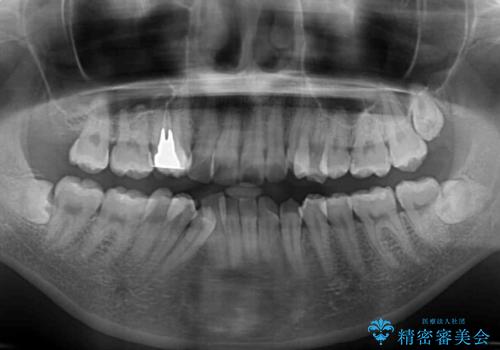

- デコボコの歯列で歯磨きがしにくいことを気にして来院された患者様です。

右側の上下は歯が重なり合って、内側に移動してしまうほどであり、それに伴って正中の位置が右側にずれている状態でした。

上下左右の第一小臼歯4本を抜歯して行うことになりますが、それだけでは咬み合わせの改善や正中位置の改善が困難であると判断されたため、アンカースクリューを用いた補助装置を併用することで、スムーズかつより良い仕上がりを目指すこととしました。

途中むし歯が見つかり、矯正治療を行いながら迅速に対応し、何とか神経組織を保存して治療を終えることができました。